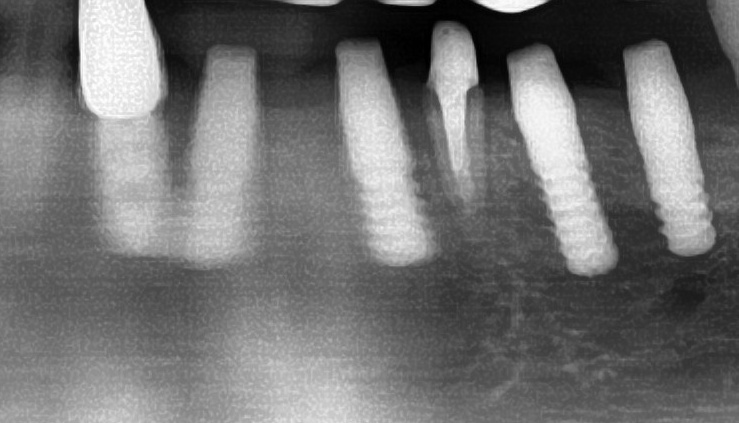

しっかりとインプラント埋め込まれた後は、動揺がないか、噛んだ時に当たらないかなどを確認して、最後にパノラマ写真を撮影して今回のオペは終了となりました。